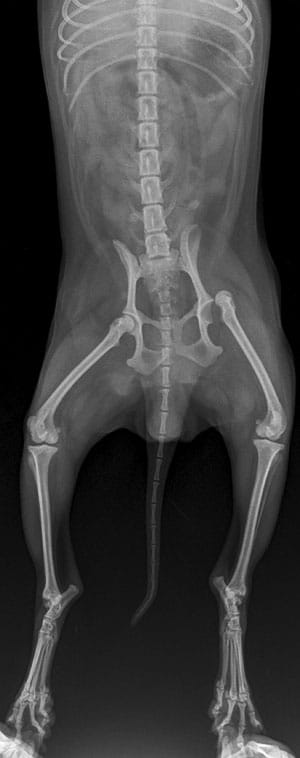

• X-rays